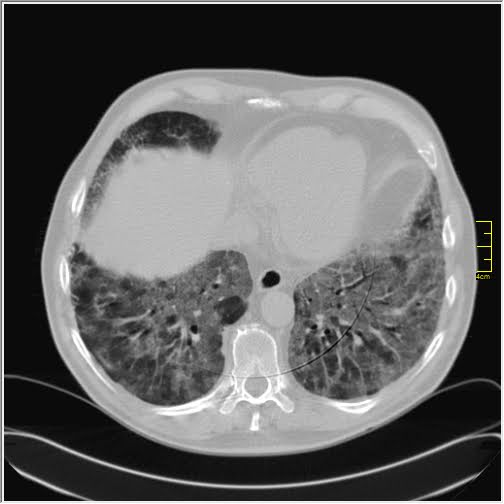

Foto: Aleksandar Ivković Foto: Aleksandar Ivković Foto: Aleksandar Ivković Zastrašujući snimci skenera pluća od 1. do 15. dana kovida autor: Božica Luković Zdravlje 26. nov. 2020. 12:33 > 26. nov. 2020. 13:35 0 Podeli vest: Kovid 19 je nepredvidiva bolest koja u razmaku od par dana može iz blage da preraste u opasnu po život. Kako koronvirus utiče na pluća iz dana u dan, pokazao je na snimcima CT skenera srpski radiolog Aleksandar Ivković. Podeli vest: Oglas Lekar iz Niša na svom blogu "Ljudi i ostale laži" redovno piše o svim važnim temama u vezi sa koronavirusom, a sada je odlučio da prikaže CT skenere pluća osobe obolele od kovida 19.Objasio je šta lekari tačno prate kada su u pitanju snimci pluća, ali i kako se te stavke menjaju kako bolest napreduje.Njegovu objavu prenosimo u celosti."Vraćam se na svoju usku struku (da ne bude da se mešam u tuđu). Kompjuterizovana tomografija, skener ili CT je metoda pregleda koja je superiorna kod zapaljenskih bolesti pluća. Kod kovida 19 se pokazala kao nezamenjiva u diferencijaciji u odnosu na ostale bolesti. Tačnost nalaza na plućima je visoka. Šta mi to možemo videti i kako tumačimo? Stvari koje pratimo su:- Ground glass konsolidacije (GGO).To su one bele "mrlje" na snimcima koje su karakteristične za ovu bolest. Nazivaju se "ground glass" svuda. Izgledaju kao da se taj deo pluća gleda kroz mlečno staklo, kao neka vrsta mikromozaika. Foto: Aleksandar Ivković | Foto: Aleksandar Ivković - Crazy paving.To su linearna zadebljanja koja se nekada vide u ground glass konsolidacijama. Ona nastaju kasnije, ne javljaju se pre GGO. Neko ih opisuje kao da pijani majstori slažu pločice. Na slikama se to vidi kao nepravilna zadebljanja unutar GGO, složena bez ikakvog reda. Foto: Aleksandar Ivković | Foto: Aleksandar Ivković - Vaskularne dilatacije. Dolazi do zapaljenskog procesa krvnih sudova i/ili do zastoja tako da su nam na snimcima krvni sudovi "deblji". Foto: Aleksandar Ivković | Foto: Aleksandar Ivković - Trakcione bronhiektazije. To su proširenja vazdušnog prostora (ali ne onog koji učestvuje u disanju) koja nastaju kada stradaju alveole i proširuje se prostor između njih. Foto: Aleksandar Ivković | Foto: Aleksandar Ivković - Arhitektonske distorzije. Pojava traka blizu pleure koje nastaju propadanja plućnog tkiva i nastanka fibroznog. Foto: Aleksandar Ivković | Foto: Aleksandar Ivković Svaki od ovih znaka se može javiti i kod drugih bolesti ali svi zajedno su specifični za kovid-19Da bi objasnili stanje koristimo Severity Score. On služi za procenu ozbiljnosti bolesti. Pluća se sastoje od pet lobusa. Procenjuje se svaki pojedinačno ocenama od 0 do 5. To znači da se skor kreće od 0 do 25.0 - znači da nema GGO konsolidacija1- znači da je manje od 5% tog lobusa zahvaćeno2 - znači da je zahvaćeno od 5 do 25% tog lobusa3 - znači da je zahvaćeno 26 do 50% tog lobusa4 - znači da je zahvaćeno 51 do 75% tog lobusa5 - znači da je zahvaćeno više od 75% tog lobusa Na CT razlikujemo 4 faze (najčešće ali nije decidirano tako) Rana faza (0 do 4. dan) - pojedinačne GGO, neka crazy paving, nizak skor Foto: Aleksandar Ivković | Foto: Aleksandar Ivković Progresivna faza (5. do 8. dan) - povećanje broja GGO i crazy paving Foto: Aleksandar Ivković | Foto: Aleksandar Ivković Pik faza (10. do 13. dan) - javljaju se konsolidacije pluća, to znači da veliki delovi pluća izgledaju kao velike bele površine a označavaju delove pluća koji su masa koja koja je u celini zahvaćena zapaljenskim procesom. Foto: Aleksandar Ivković | Foto: Aleksandar Ivković Faza rezolucije (posle 14. dana) - vraćanje delova pluća u normalu ili smrt Foto: Aleksandar Ivković | Foto: Aleksandar Ivković Iskustveno smo došli do skora 15 koji predstavlja neku granicu između verovatno dobrog i verovatno lošeg ishoda. Samo tumačenje zavisi od faze bolesti. Naš nalaz je samo deo procene i ne menja laboratorijske i pulmološke, kao ni ostale. Svaki nalaz zajedno daje ukupnu sliku bolesti. Foto: Aleksandar Ivković | Foto: Aleksandar Ivković Nalaz je u88% slučajeva sa obe strane,88% ground glass,80% posteriorno,79% multilobularno,76% periferno i30% konsolidacijeTo je posao radiologa, to je moj posao. Sasvim sigurno je da bez ovih slika lečenje ne bi bilo lako. Pacijente delimo na lake - one koji nemaju tegobe, teške - one koji imaju zahvaćeno do 50% pluća i kritične a to su oni kod kojih je više od 50% zahvaćeno", piše dr Ivković.***Bonus video:https://www.youtube.com/watch?v=fYeYlhqeD5cPratite nas i na društvenim mrežama:FacebookTwitterInstagram Revolucija iz Niša: Test na koronu koji predviđa tok bolesti Zdravlje 0 Tekst naučnika koji ruši sve zavere o koroni - i daje nadu Zdravlje 0 72 sata pakla od kad su me zabolela pluća u kovid Srbiji Zdravlje 0 aleksandar ivković ct skener koronavirus kovid-19 pluća Pratite nas na društvenim mrežama: Koje je tvoje mišljenje o ovoj temi? Učestvuj u diskusiji ili pročitaj komentare Budite prvi koji će ostaviti komentar Pošalji komentar Pročitaj komentare (0)